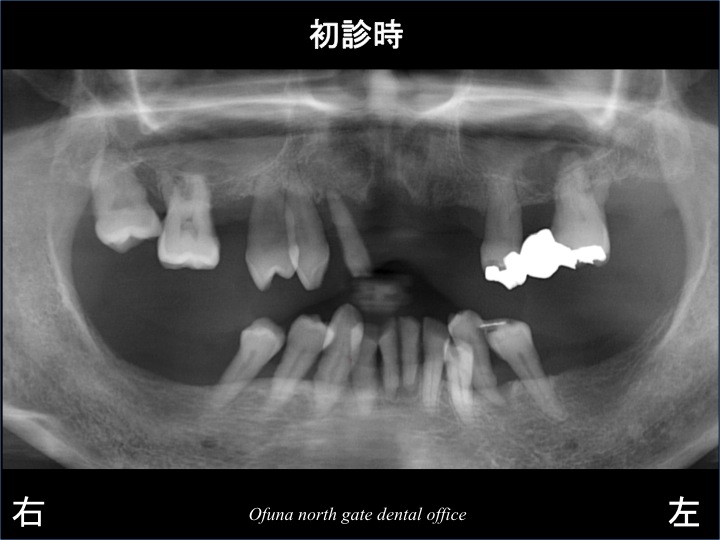

初診時に上顎の歯がグラグラして噛めないとのことで来院された方です。

検査をしてみると上顎の歯は、ピンセットでも取れそうなくらい グラグラしています。

下顎は、奥歯が欠損しており、義歯(入れ歯)は使用していませんでした。

歯周病により骨吸収 が起こっていました。

以下の写真は、骨吸収を表したレントゲン写真です。

青線は、本来の骨の位置です。

赤線は、現在の骨の位置です。

つまり、骨吸収が起こっているのです。

上顎前歯部は、根の先まで骨がないのがわかるかと思います。

歯周病の検査の結果、ほとんどの歯は、保存が難しい状態でした。